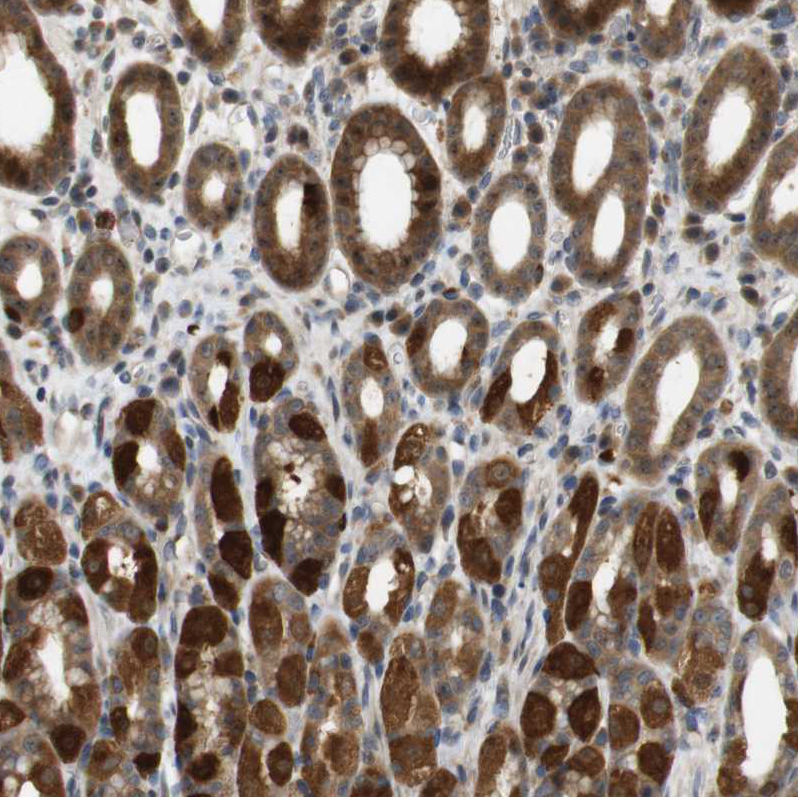

Immunohistochemical staining of human stomach shows strong positivity in cytoplasm granular in glandular cells.